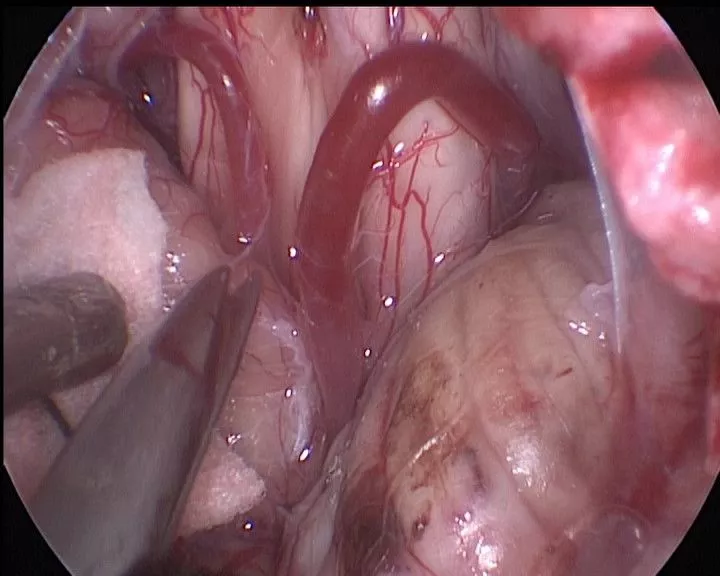

抬起小脑蚓,暴露并剪开蛛网膜小梁

电凝一侧小脑蚓部使之回缩

抬起对侧小脑蚓,剪开蛛网膜小梁

分离对侧小脑蚓和PICA的粘连

分离小脑谷,寻找四脑室正中孔